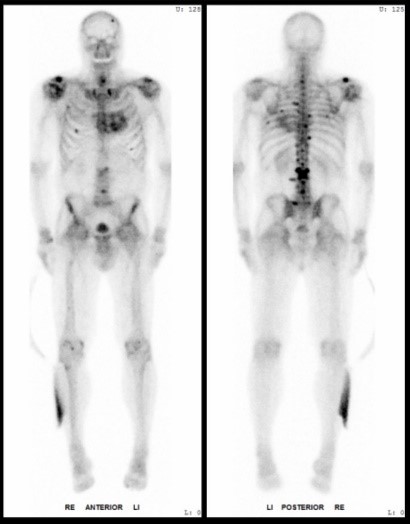

In der interventionellen Radiologie beschränkt sich die Tätigkeit des Radiologen nicht allein auf die bildgebende Diagnostik. Vielmehr übernimmt er eigenständig minimalinvasive Eingriffe und trägt dabei die Verantwortung für die prä-, peri- und postoperative Versorgung der Patient: innen.